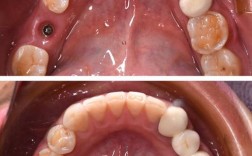

| 提升美学效果 | 尤其在前牙区,即刻种植可精准植入种植体,模拟天然牙的倾斜角度与位置,配合临时冠引导牙龈成形,有效避免“黑三角”或牙龈萎缩等美学问题。 |

- 缝合与处理:无张力缝合牙龈,关闭拔牙窝创口;若骨量充足,可同期制作临时修复体(树脂材料),调整咬合避免早接触。

- 永久修复:骨结合完成后(通常3-4个月),取模制作全瓷冠或烤瓷冠,完成最终修复,并强调口腔卫生维护(使用牙线、冲牙器,定期洁牙)。

- 美学并发症:前牙区牙龈萎缩或“黑三角”,需通过数字化设计精准植入种植体,配合临时冠诱导牙龈成形。